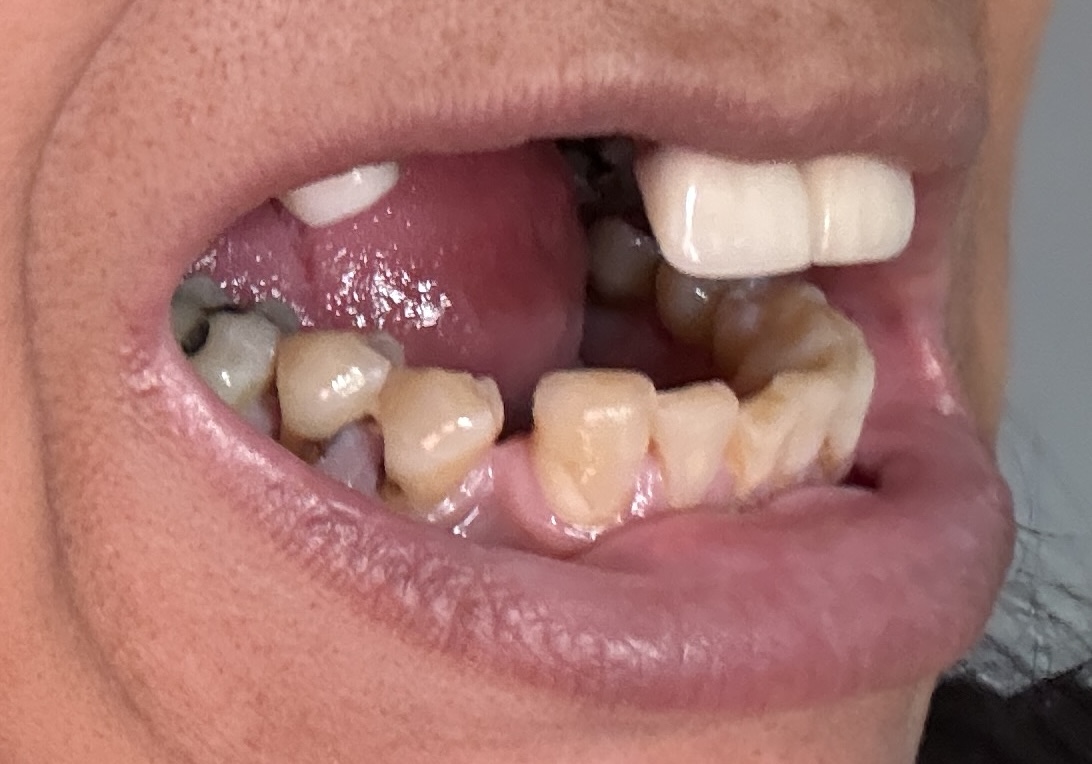

Overall information (upper arch)

12,13,14 have had root canals in past and now have quite a bit movement. 2-5 have all had root canals in past and now the crowns are breaking down.

Overall information (lower arch)

Overall, all of my gums have receded and most of the bottom teeth are exposed w/ some roots and there are many cavities.